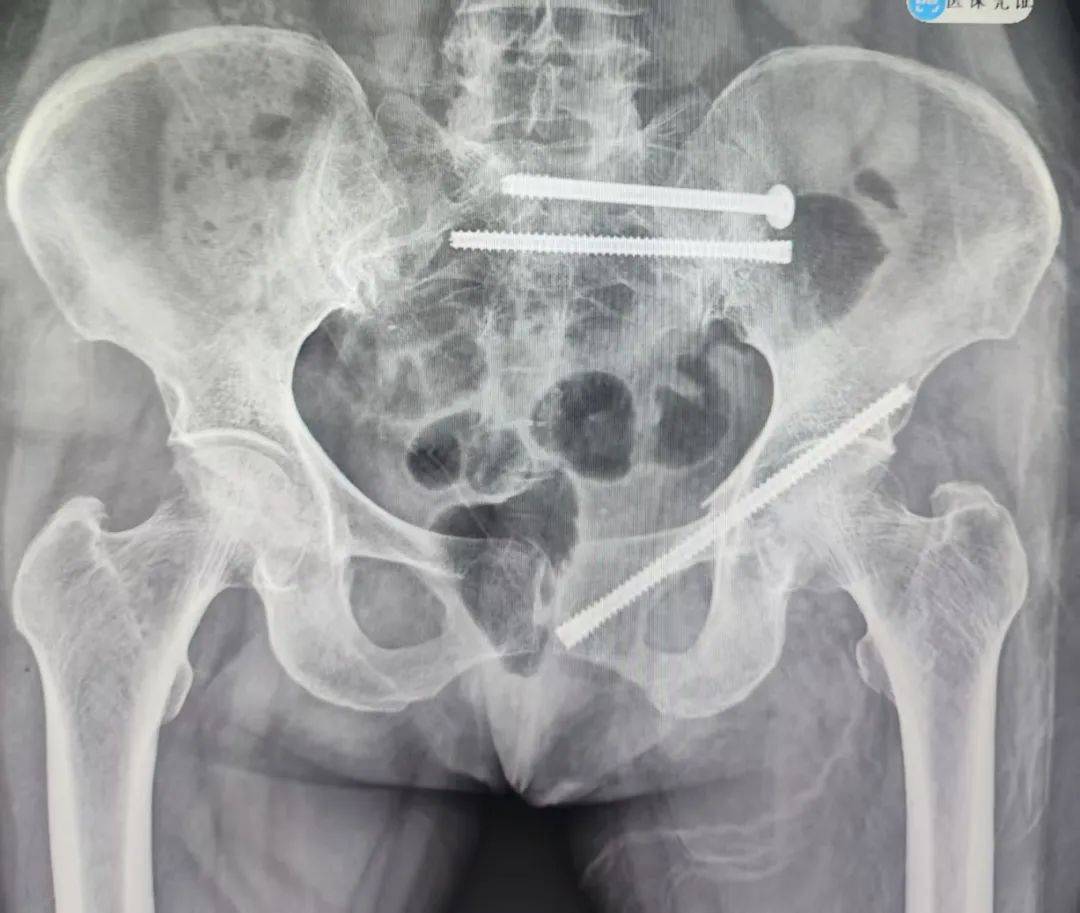

经过充分的术前准备,急诊科团队决定为姬奶奶实施骨盆骨折通道螺钉内固定术。与传统手术相比,它具有创伤小、恢复快、并发症少等诸多优势。手术室内,气氛紧张而严肃。医生们全神贯注,凭借着精湛的技术和丰富的经验,精准地将螺钉植入姬奶奶的骨盆骨折部位,固定骨折断端。每一个动作都小心翼翼,每一个步骤都精准无误,整个手术过程如行云流水般顺畅。

术后当晚,姬奶奶就能够自行坐起。这一小小的动作,对于经历了病痛折磨的她来说,无疑是一个巨大的胜利。

术后第二天,姬奶奶更是已经能够顺利下床活动。在病房里,她在家人的搀扶下,小心翼翼地迈出每一步。虽然步伐还有些蹒跚,但她的脸上洋溢着久违的笑容,那笑容如同春日里的阳光,温暖而灿烂。